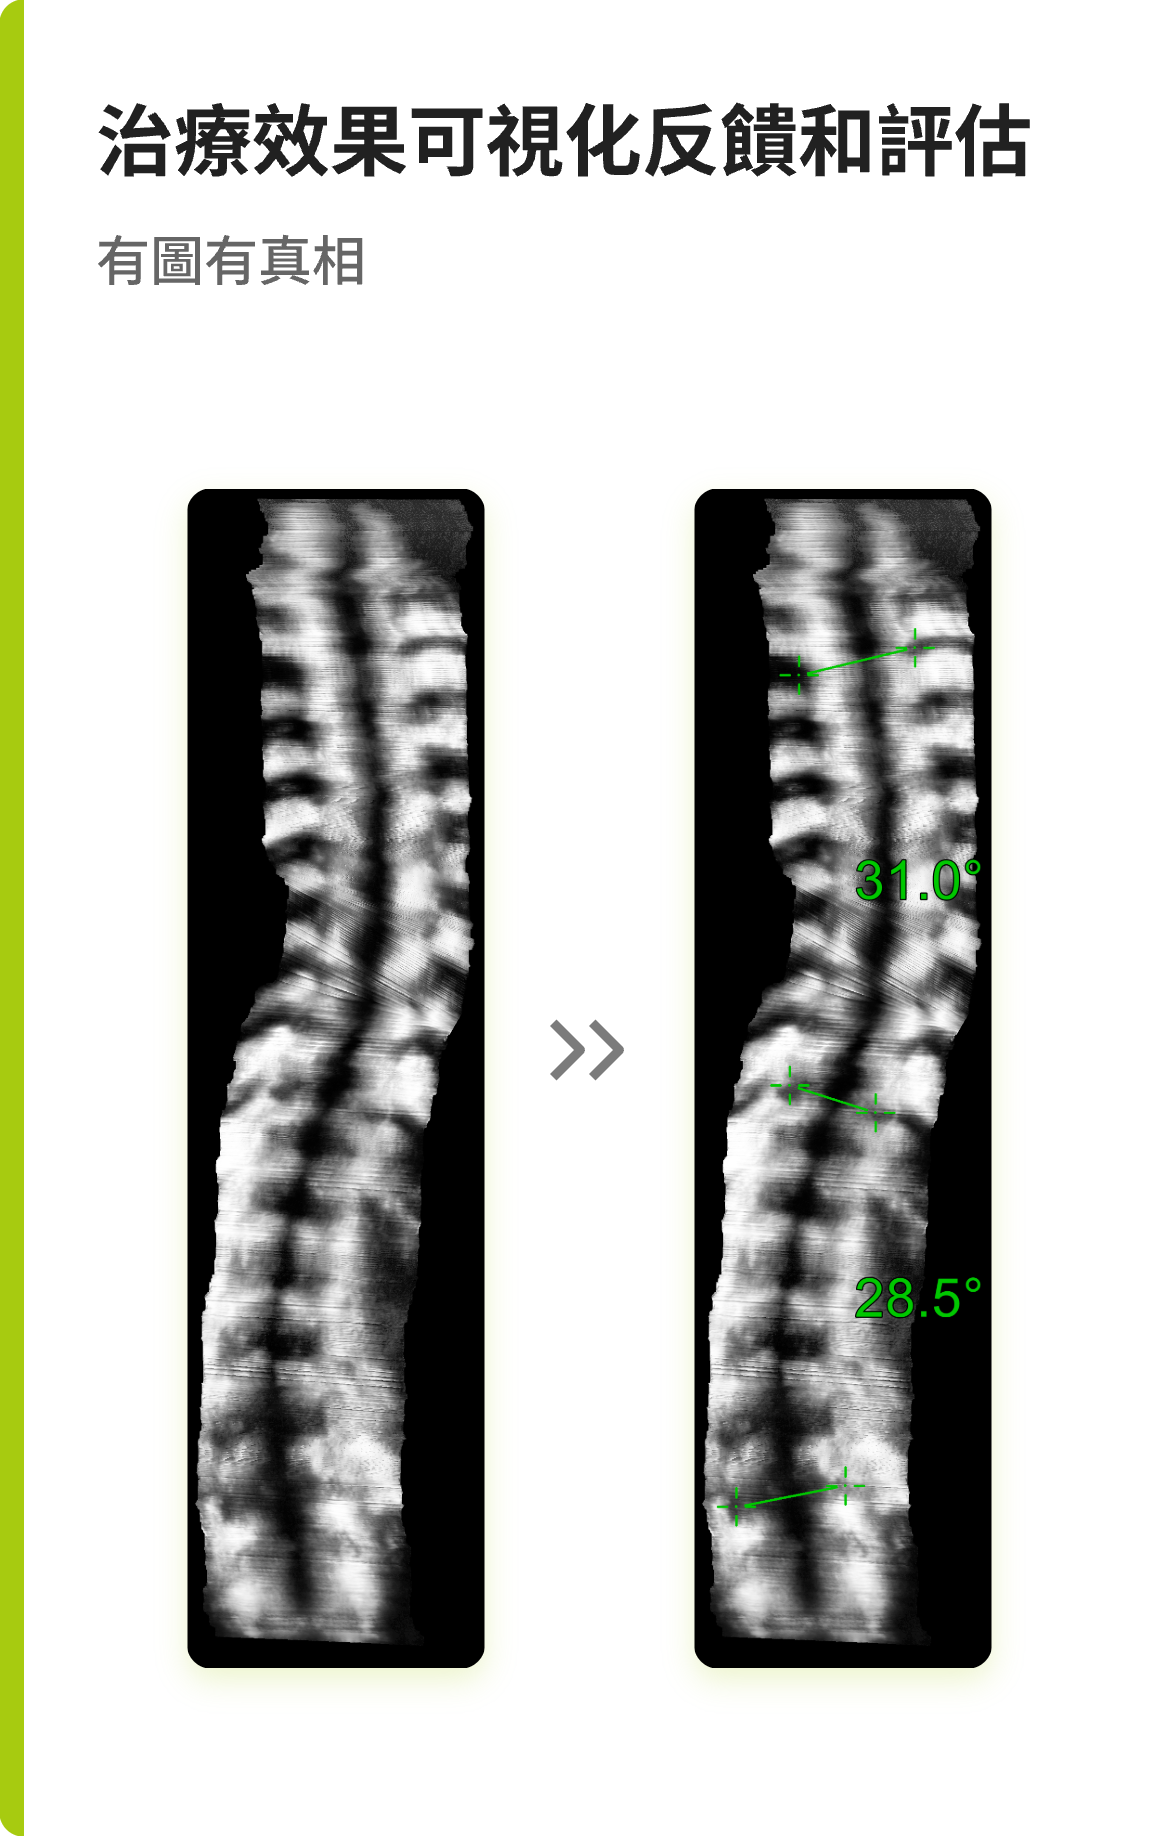

“ 獲取脊柱T1-L5全長冠狀位超聲圖像•定量評估脊柱側彎程度 ”

Scolioscan Air AI 輔助測量算法可以自動識别脊柱特征點并測量每一節椎體角度,幫助醫生快速計算脊柱彎曲角度,大幅縮短報告生成時間,提升檢查效率。